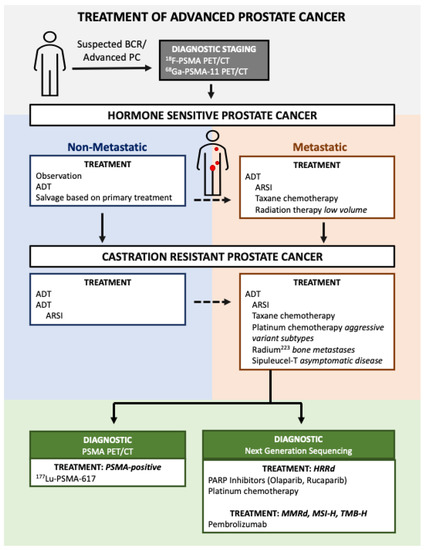

PARP Inhibitors in Metastatic Castration-Resistant Prostate Cancer: Whom to Treat?